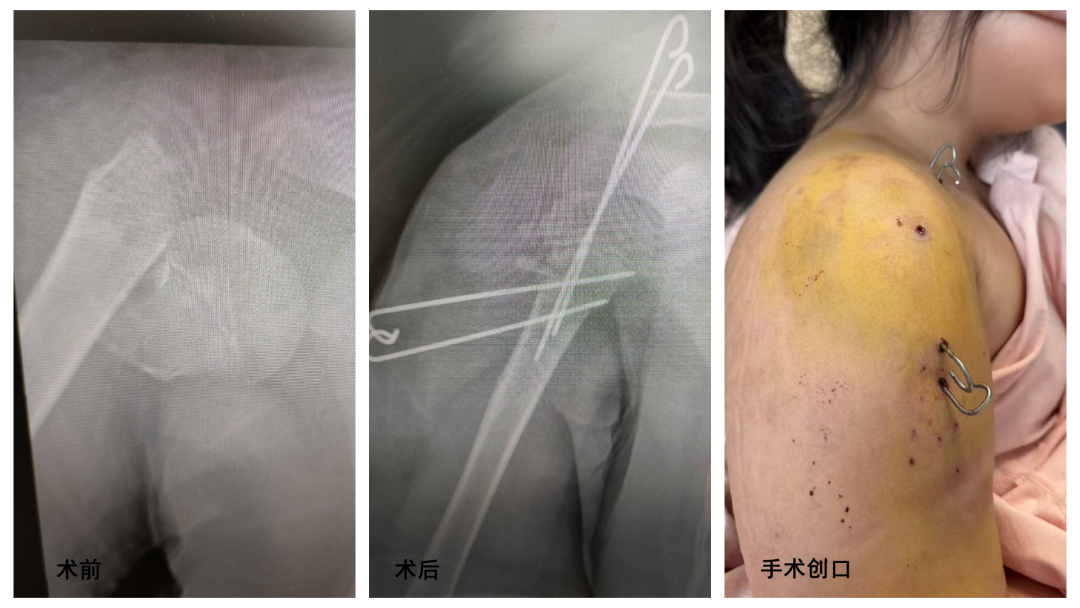

兒童骨折治療與成人有著本質(zhì)區(qū)別,需兼顧“復(fù)位精準(zhǔn)”與“微創(chuàng)保護”。針對小悅?cè)坏墓钦垲愋停f偉帶領(lǐng)團隊經(jīng)過全面評估,決定采用閉合復(fù)位微創(chuàng)技術(shù)——這一技術(shù)正是兒童骨科的特色優(yōu)勢,能最大程度減少對患兒骨骼及周圍軟組織的損傷。

手術(shù)中,醫(yī)生無需大刀闊斧切開皮膚,僅通過體表定位和X線精準(zhǔn)引導(dǎo),便可將移位的骨折端準(zhǔn)確復(fù)位;隨后經(jīng)皮置入固定物,實現(xiàn)牢固固定。整個手術(shù)創(chuàng)口僅如米粒般大小,術(shù)后幾乎不留疤痕,堪稱一場“隱形修復(fù)”。“原本以為孩子要遭大罪,沒想到手術(shù)這么精細(xì),幾乎看不到傷口!”親眼見證手術(shù)效果后,家長表示滿意。